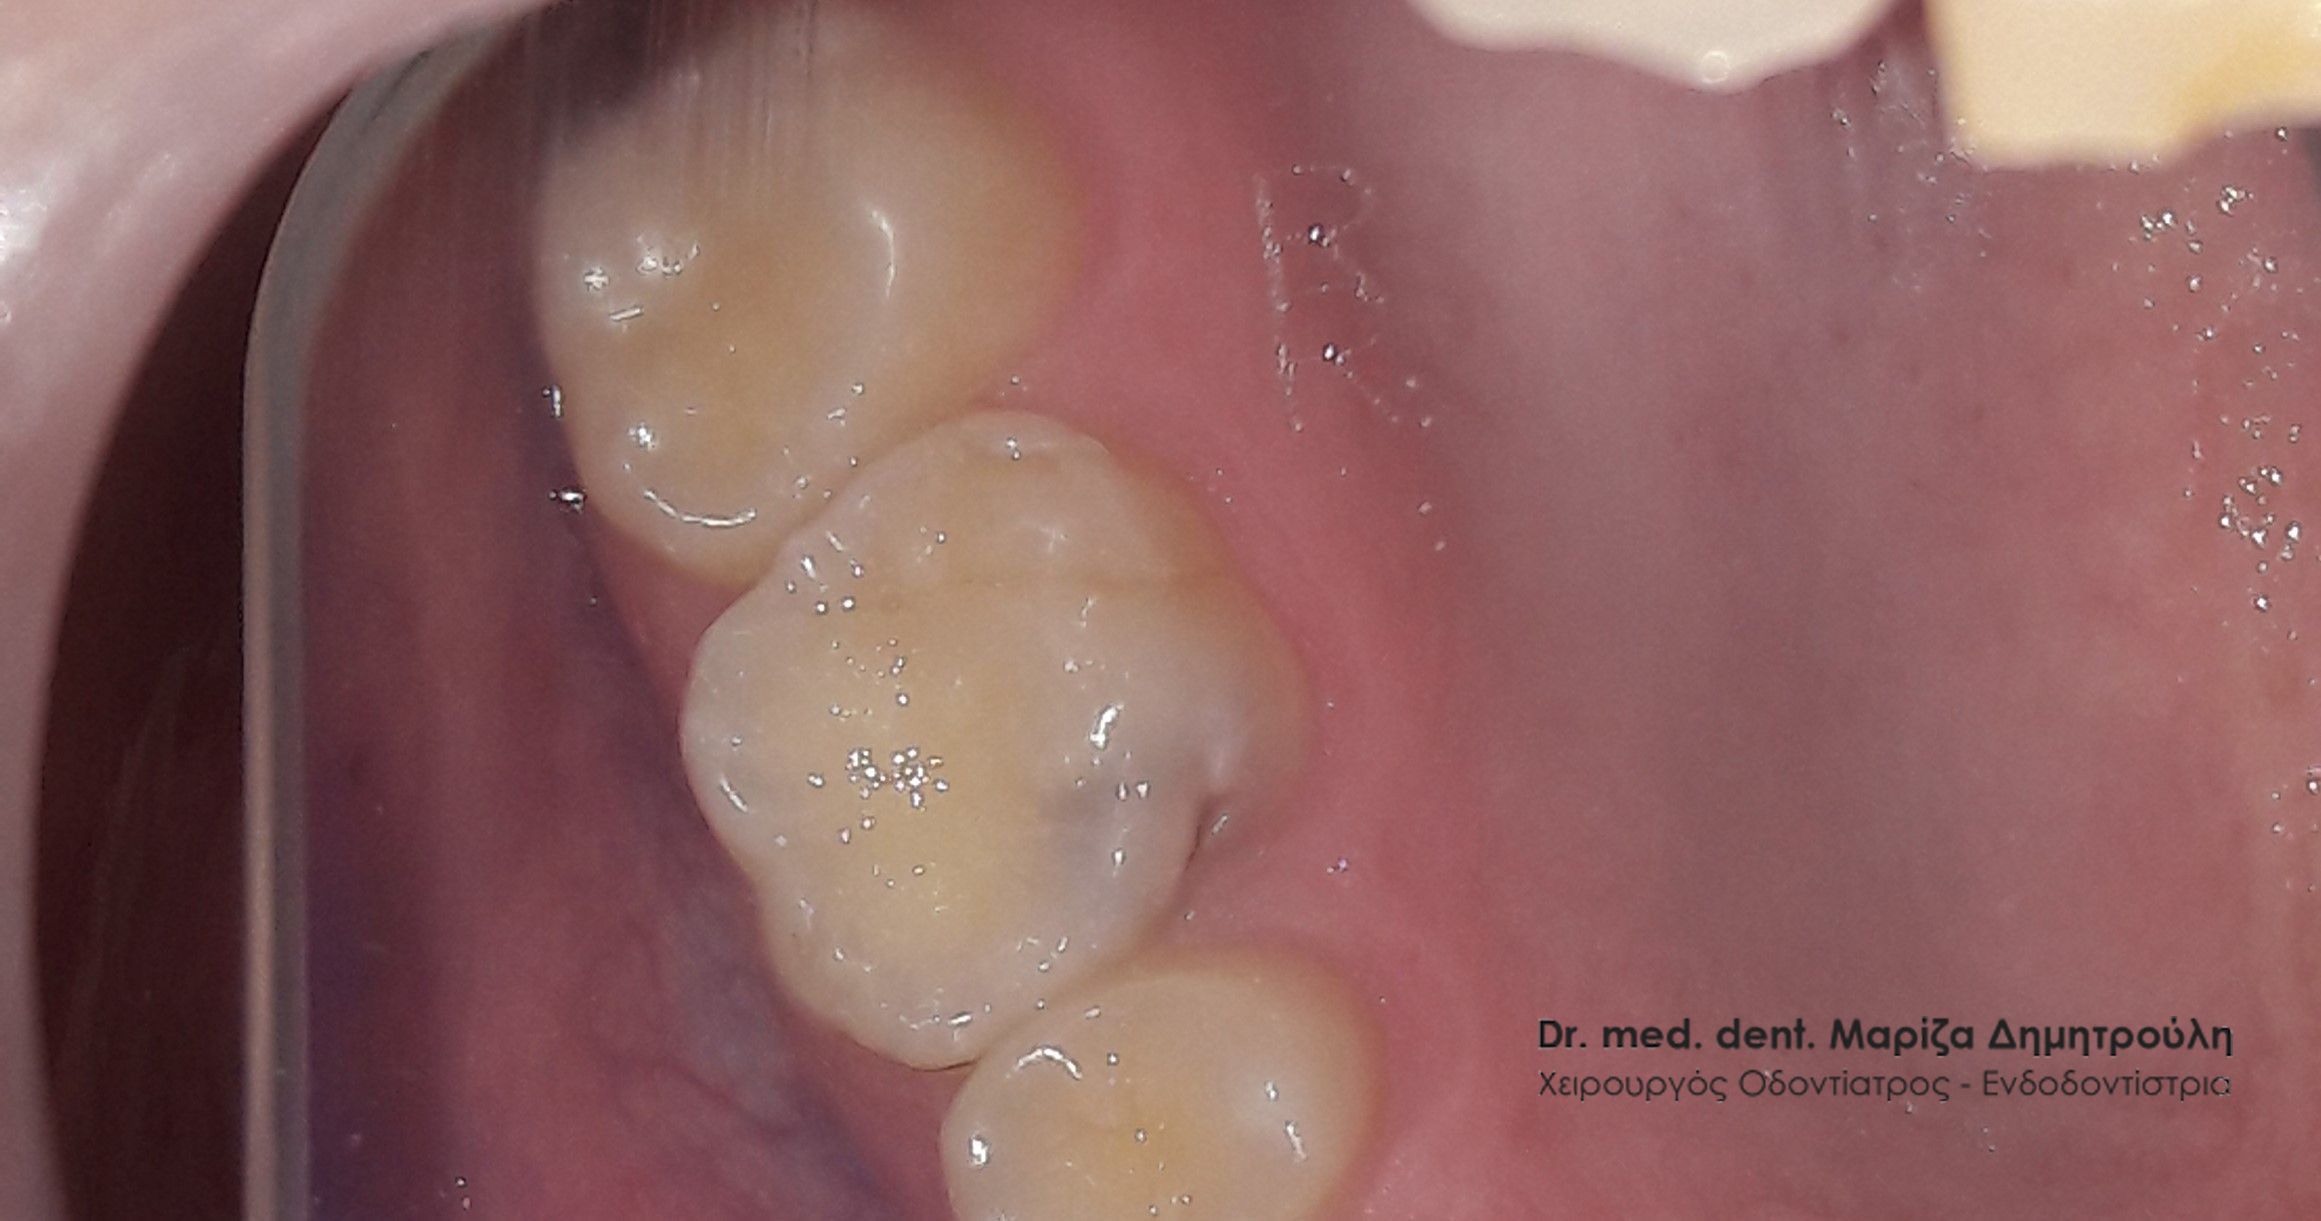

Η ασθενής επισκέφτηκε το ιατρείο καθώς πονάει αρκετά όταν μασάει στη δεξιά πλευρά της άνω γνάθου. Μετά την κλινική και ακτινογραφική εξέταση της περιοχής διαπιστώθηκε η παρουσία μιας βαθιάς “κρυμμένης” τερηδόνας στον πρώτο άνω δεξιό γομφίο. Σε συνεννόηση με την ασθενή αποφασίστηκε η διάνοιξη του δοντιού και η αποκατάστασή του με λευκό σφράγισμα σύνθετης ρητίνης. Π

Αρχικά χορηγήθηκε τοπική αναισθησία στην περιοχή του πονεμένου δοντιού και ξεκίνησε ο εκτροχισμός του. Η διάνοιξη του δοντιού πράγματι αποκάλυψε την ύπαρξη βαθιάς τερηδόνας, όπως δείχνουν και οι φωτογραφίες. Ακολούθησε η απομάκρυνση της τερηδόνας, η τοποθέτηση ειδικού υλικού για την προστασία του νεύρου του δοντιού και τέλος το οδοντικό έλλειμμα αποκαταστάθηκε με λευκό σφράγισμα.

Το δόντι είναι πλέον ασυμπτωματικό και η ασθενής μπορεί να μασάει χωρίς ενόχληση από τη δεξιά πλευρά της άνω γνάθου.

ΠΡΙΝ

Η έκταση της τερηδόνας μετά τη διάνοιξη της κοιλότητας

ΜΕΤΑ